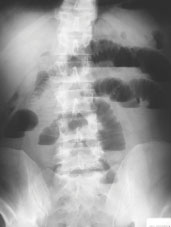

41-letni moški je bil sprejet na naš oddelek z razvijajočo se sliko ileusa tankega črevesa. V preteklosti je že bil operiran zaradi levostranske dimeljske kile, imel pa je tudi reponibilno desnostransko dimeljsko kilo ter čakal na operacijo. SH levo predoperativno ni bila klinično izražena, zato nanjo nismo pomislili. Rentgenska slika abdomna stoje na prazno je potrdila ileus tankega črevesa (Sl. 4), ki ga s konzervativnimi ukrepi nismo uspeli razrešiti, zato je bil urgentno operiran. Pri operaciji smo našli v levostransko SH vkleščeno tanko črevo. Narejena je bila dezinkarceracija vijuge ter notranja evakuacija črevesne vsebine. Vijuga ni bila vitalno ogrožena. V pooperativnem poteku je prišlo do paralitičnega ileusa, ob konzervativnih ukrepih se je peristaltika po petih dneh vzpostavila.